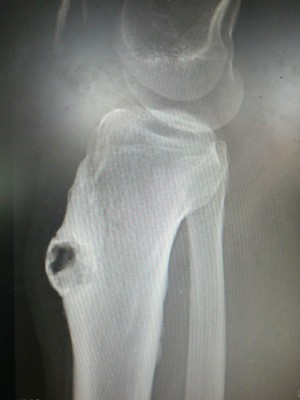

3.晚期表现为已发生骨膜下的骨质增生,这时候必须要去医院就医,自己能做的就是热敷和按摩,在不加重疼痛的情况下要进行伤肢的功能性锻炼。下图为X光下的胫骨骨质增生侧面观。